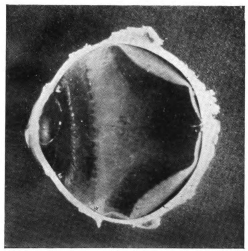

PLATE II.

FACING

PAGE

10.

LENS DISLOCATED BETWEEN CILIARY BODY AND SCLERA

curly bracket span

38

11.

NUCLEUS OF CATARACT FREELY MOVABLE BETWEEN THE AQUEOUS AND VITREOUS CHAMBERS

12.

LENS IMPACTED IN ANGLE OF ANTERIOR CHAMBER

13.

CAPSULE OF MORGAGNIAN CATARACT IMPACTED IN ANGLE OF ANTERIOR CHAMBER

14.

LENS FLOATING FREE IN VITREOUS CHAMBER

15.

LENS LIGHTLY IMPRISONED IN EXUDATE INTO VITREOUS CAVITY